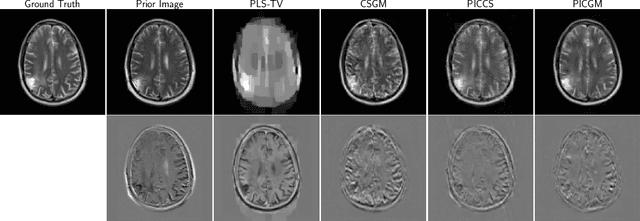

Abstract:Computed medical imaging systems require a computational reconstruction procedure for image formation. In order to recover a useful estimate of the object to-be-imaged when the recorded measurements are incomplete, prior knowledge about the nature of object must be utilized. In order to improve the conditioning of an ill-posed imaging inverse problem, deep learning approaches are being actively investigated for better representing object priors and constraints. This work proposes to use a style-based generative adversarial network (StyleGAN) to constrain an image reconstruction problem in the case where additional information in the form of a prior image of the sought-after object is available. An optimization problem is formulated in the intermediate latent-space of a StyleGAN, that is disentangled with respect to meaningful image attributes or "styles", such as the contrast used in magnetic resonance imaging (MRI). Discrepancy between the sought-after and prior images is measured in the disentangled latent-space, and is used to regularize the inverse problem in the form of constraints on specific styles of the disentangled latent-space. A stylized numerical study inspired by MR imaging is designed, where the sought-after and the prior image are structurally similar, but belong to different contrast mechanisms. The presented numerical studies demonstrate the superiority of the proposed approach as compared to classical approaches in the form of traditional metrics.

Abstract:Obtaining an accurate and reliable estimate of an object from highly incomplete imaging measurements remains a holy grail of imaging science. Deep learning methods have shown promise in learning object priors or constraints to improve the conditioning of an ill-posed imaging inverse problem. In this study, a framework for estimating an object of interest that is semantically related to a known prior image, is proposed. An optimization problem is formulated in the disentangled latent space of a style-based generative model, and semantically meaningful constraints are imposed using the disentangled latent representation of the prior image. Stable recovery from incomplete measurements with the help of a prior image is theoretically analyzed. Numerical experiments demonstrating the superior performance of our approach as compared to related methods are presented.